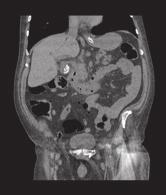

Muž (79 let) byl přivezen záchrannou službou na urgentní příjem pro celkové zhoršení stavu a slabost trvající asi 14 dní. Anamnestické údaje zahrnovaly nikotinizmus, CHOPN, hypertenzi, hyperlipidemii, diabetes mellitus 1. typu, obezitu. Pacient dlouhodobě užíval antihypertenziva, statin, inzuliny, NSA (Meloxicam) při bolesti – užíval jej maximálně 1× denně. Mezi subjektivními obtížemi dominovaly řadu dnů trvající obtíže – celková slabost, únava, udával také bolesti v pravém podžebří a zvracení. Objektivně bylo břicho bolestivé v pravém epigastriu, ve stejném místě byla hmatná i tuhá rezistence.

Laboratorně jsme zjistili hyperglykemii 18,6 mmol/l, minerálový rozvrat –hyponatremii 125 mmol/l, hyperkalemii 5,6 mmol/l, známky dehydratace renální insuficience – urea 23,8 mmol/l, kreatinin 316 umol/l, laktát 3,2 mmol/l. Byla přítomna zvýšená zánětlivá aktivita, CRP 90mg/l. V krevním obraze dominovala těžká anemie (Hgb 50g/l), trombocytóza 676 × 109/l, byla přítomna spontánní koagulopatie. Hodnoty jaterních testů byly v normě.

Provedli jsme sonografii břicha s nálezem hydropsu žlučníku se sludge, konkrementy v krčku žlučníku, gastrektazie.

Pacientovi jsme zavedli nazogastrickou sondu, která odvedla 1 000ml stagnačního obsahu. K dalšímu objasnění patologie bylo provedeno nativní CT břicha (zvýšená hladina kreatininu).

Pacienta jsme po konzultaci s radiologem a chirurgem indikovali k operačnímu výkonu.

Otázka:

Co vidíme na CT snímcích (obr. – )? Jaká je diagnóza a prognóza našeho pacienta? Správnou odpov a komentá naleznete v p íštím ísle.